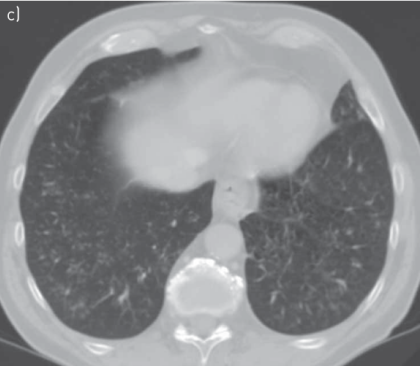

(1)急性间质性肺炎(AIP)/急性呼吸窘迫综合征(ARDS)/弥漫性肺泡损伤(DAD):弥漫性或多灶性磨玻璃影(GGO)或实变,并伴有肺容量减少和牵引性支气管扩张[17]

图片

(2)隐源性机化性肺炎(COP):是NSCLC中最常见的CIP类型,双侧多灶性实变,周围和下肺分布,伴有GGO和网状阴影[17]